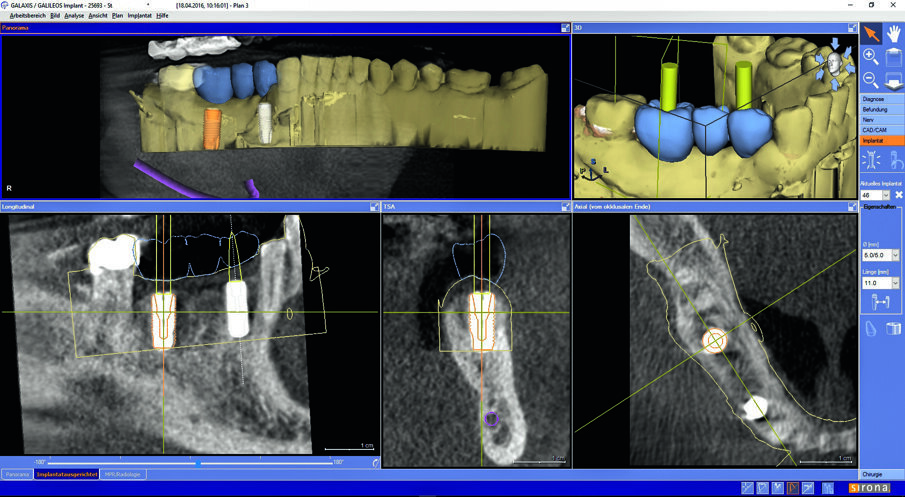

In this case, an Orthophos SL 3D from Dentsply Sirona was used for both panoramic and DVT scans. Digital impressions of the patient were taken with a CEREC camera and implant planning took place within the Galileos Implant software. For guided surgery, the team used CEREC Guide 2 milled in-house at their dental laboratory on an inLab MC X5 milling machine.

Matching of Orthophos SL 3D data with the prosthetic proposal in Galileos Implant.

Prosthetic alignment of the implant in planning.

By means of a low-dose recording, the implant was checked three-dimensionally.

The patient opted for a treatment plan involving the insertion of two implants and then an implant-supported bridge. Digital imaging, combining DVT with CEREC optical impressions were used to plan the implant surgery in Galileos Implant software.

The software creates an implant proposal as well as enables planning of the alignment of the prosthetic. The ability to plan and perform virtual surgery allowed the team to maximize safety and minimize risk. CEREC Guide 2 was chosen in the treatment plan and then milled in our practice to use during surgery.

An additional DVT image was made in the Orthophos SL’s Low Dose Mode as a check post-implantation. We chose hybrid abutments on ti-base for the final restoration.